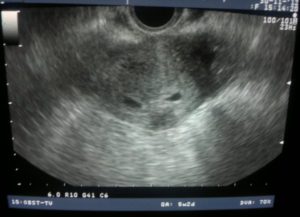

В этот же период начинается рост плаценты – уникального органа, обеспечивающего защиту и питание плода. Из трофобласта и эктодермы образуются амнион и хорион. Амниотическая полость заполняется околоплодными водами, а хорион начинает активно продуцировать ХГЧ. Размеры эмбриона достигают значения в 4 мм и его уже можно увидеть на УЗИ.

После проведения анализа на содержание в крови хорионического гонадотропина женщина уже может знать, что она носит в себе новую жизнь. Спустя 3 недели беременности, что происходит с плодом – можно разглядеть с помощью ультразвукового исследования.

На этом этапе эмбрион представляет собой крошечный шар с едва различимыми головным и хвостовым концами, окруженный плодным яйцом. УЗИ-диагностика на ранних сроках беременности проводится двумя способами:

Именно УЗИ на третьей неделе после введения эмбрионов является методом, позволяющим достоверно определить наличие беременности, так как ЭКО, к сожалению, не всегда может гарантировать удачный результат.